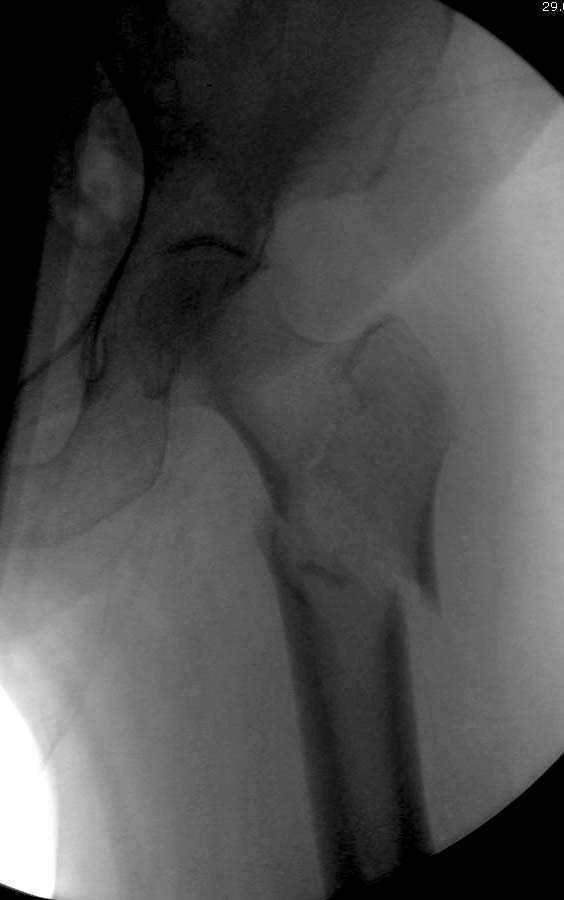

Здесь представлен случай, где в послеоперационном периоде обнаружена техническая ошибка, Gamma 3 установлен с нарушением методики. Больная в 91 лет, прооперирована через день после поступления и выписана через 48 часов.<br>

При первом послеоперационном поликлиническом осмотре больная предъявила жалобы на боли в бедре. В серийных снимках обнаружен продольный перелом верхнего отдела бедра.<br>

Считаем, что техническая ошибка произошла во время установки гвоздя, когда рассверливанию канала не уделили должного внимания. Канал остался узковат, и гвоздь был забит с силой.

Имя     : Gamma 3. 4.jpg